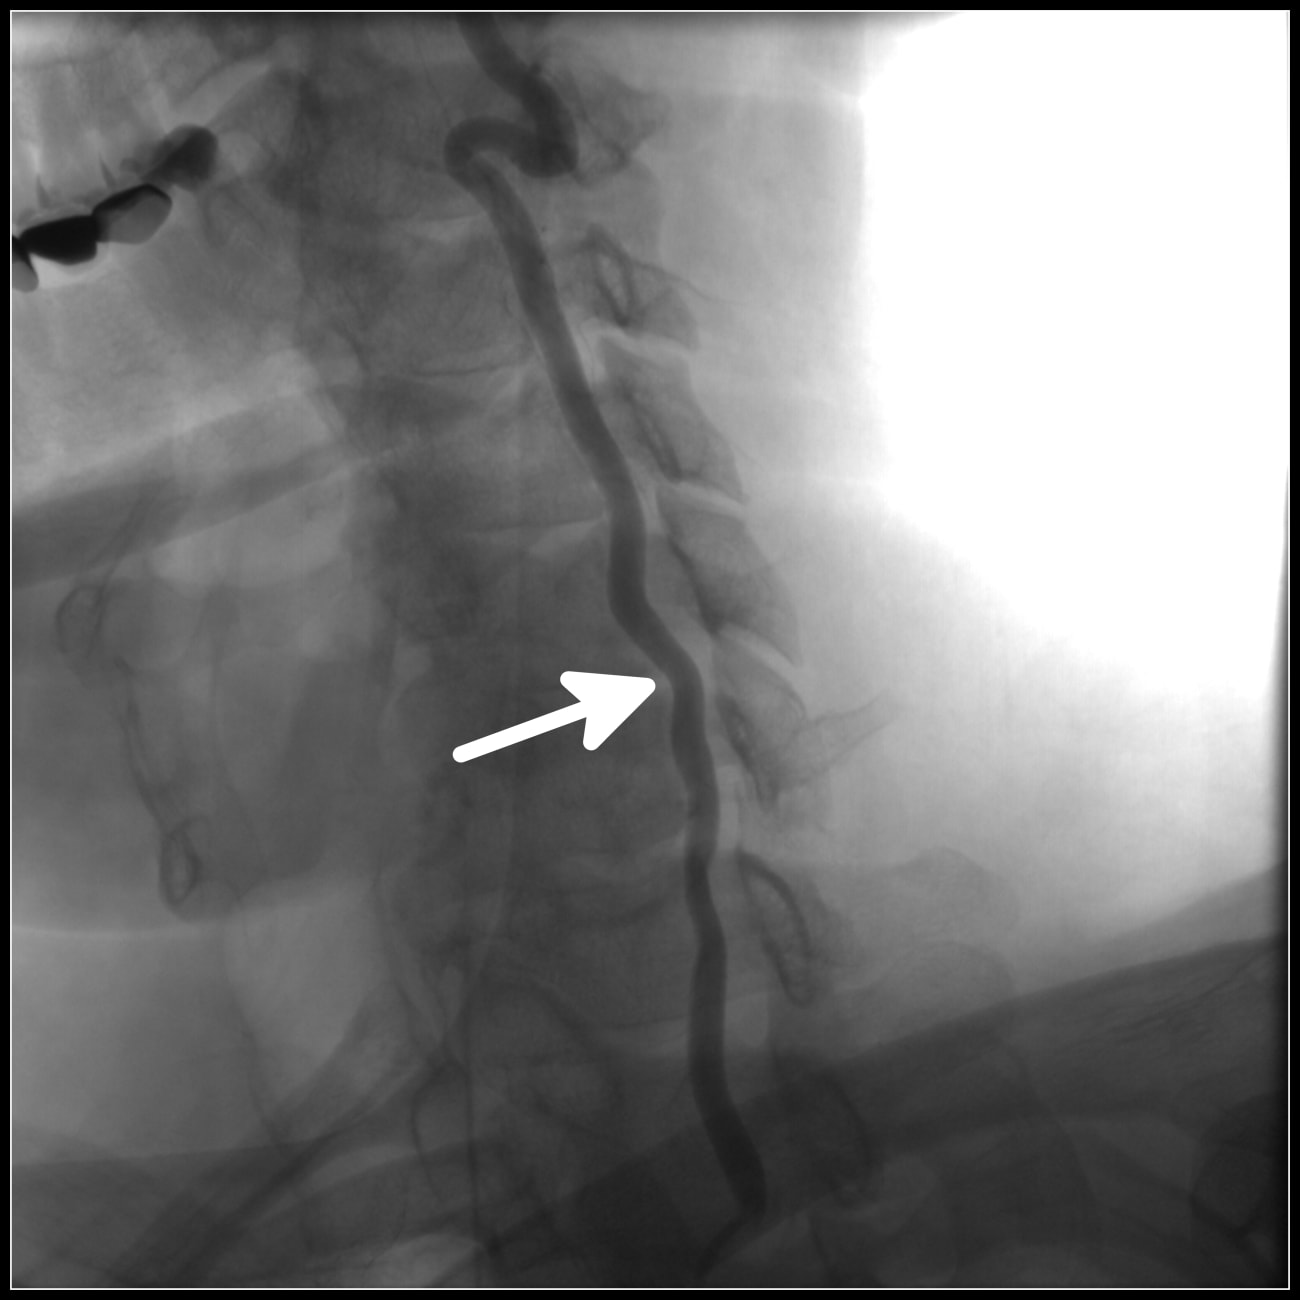

Spinal Cord Stimulation Dayton Orthopaedic Surgery

From daytonorthopedicsurgery.com

From studylib.net

Spinal Cord Stimulation Spinal Cord Stroke Physical Therapy These recommendations are intended as a guide for clinicians to. (1) we suggest rehabilitation be offered to. Based on the findings from the systematic review, our recommendations were: These recommendations are intended as a guide for clinicians to optimize rehabilitation outcomes for persons with chronic stroke, incomplete spinal cord injury, and traumatic brain injury to improve walking speed and distance.. Spinal Cord Stroke Physical Therapy.